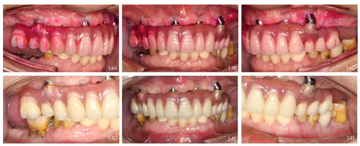

治疗结果:上颌即刻固定义齿试戴,义齿被动就位顺利,咬合关系恢复至第二前磨牙,义齿螺丝加力至15Ncm。检查患者前牙区覆

覆盖关系恢复正常,唇侧丰满度良好,双侧后牙区咬合关系稳定(图5,图6),患者满意。

即刻修复6个月后佩戴上颌终义齿,咬合关系恢复至第一磨牙,4颗种植体螺丝被动就位后分别加力至15Ncm。口内检查:中线、义齿边缘交界线、义齿切缘曲线、

平面、覆

覆盖关系、双侧磨牙咬合关系均良好(图7,图8,图9)。

随访及转归:上颌种植固定义齿修复5年,每年定期复查,修复体完整稳固,无机械并发症发生;种植体周围软组织健康稳定(图11A~I,图12A~I,图14)。

随访X线检查示4颗种植体周围骨结合良好(图10,图11J,图12J,图13,图15)。